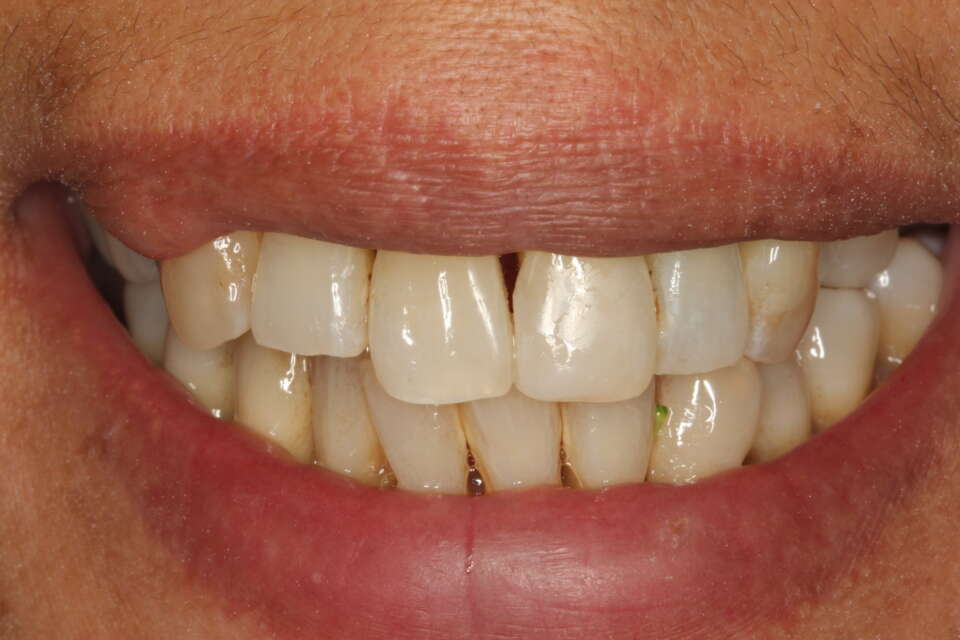

After treatment

IMG 7926

A few months later, a new smile!